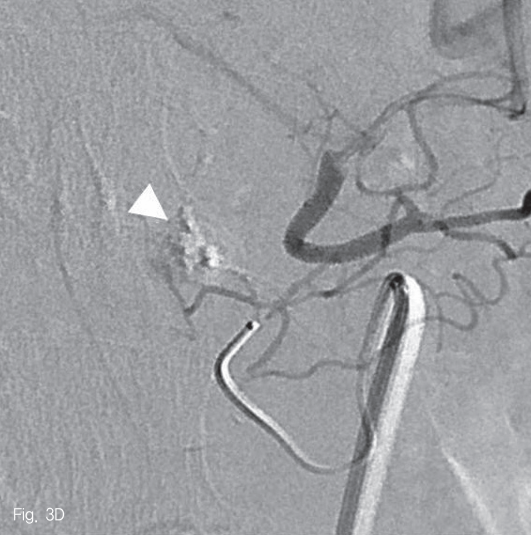

Arteriogram of superior mesenteric artery (SMA) shows a small pseudoaneurysm originating from the middle colic artery (A-C, arrowheads) which has large angle to backward (A). After the superselection of the bleeding branch (C), embolization with 33% glue was performed without any complication (D).

Fig 3D

우측 대퇴동맥을 천자하여 5-Fr sheath(Radifocus; Terumo, Tokyo, Japan)를 삽입한 뒤, 5-Fr Cobra catheter(Cook Medical Inc, Bloomington, USA)를 사용하여 상장간막동맥 조영술을 시행하였다. 중간결장동맥의 근위부에 조영제가 채워지는 낭모양의 가성동맥류가 보였다 (Fig. 3A). 중간결장동맥은 상장간막동맥에서 후방으로 기시하여 5-Fr catheter로 선택하기 어려웠다. 0.035-in shapeable guidewire(Radifocus; Terumo, Tokyo, Japan)를 이용하여 중간결장동맥의 근위부까지 5-Fr catheter로 진입하였다 (Fig. 3B). 2.0-Fr microcatheter (Progreat; Terumo, Tokyo, Japan)를 이용해서 병변 직전까지 초선택하였다 (Fig. 3C). N-butyl-2-cyanoacrylate (Histocryl; B. Braun, Tuttlingen, Germany)과 Lipiodol (Guerbet, Paris, France)을 1:2 비율로 섞은 용액(33% glue)으로 색전술을 시행하였고 가성동맥류는 소실되었다 (Fig. 3D). 시술 직후 환자는 통증을 호소하였지만 곧 호전되었다.